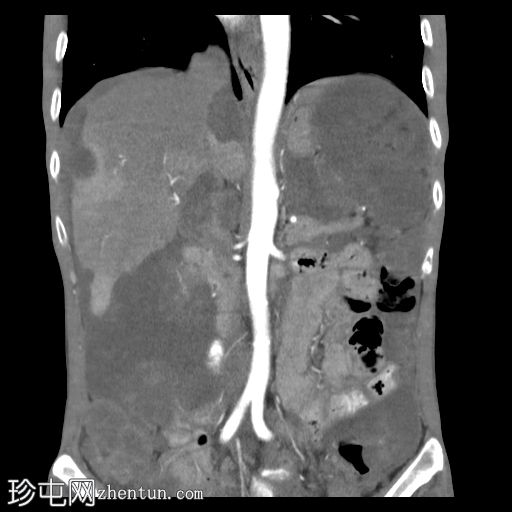

冠状位增强扫描(动脉期)

大网膜和肠系膜内可见低密度、不均匀的腹膜积液,脏器表面呈扇形凹陷,尤其以肝脏和脾脏最为明显。

直肠穹窿可见一处厚度 1.2 cm、长 4.0 cm 的增强壁增厚。可见病灶周围及骶前淋巴结肿大,最大者直径 1.6 cm。

左下腹可见末端结肠造口。